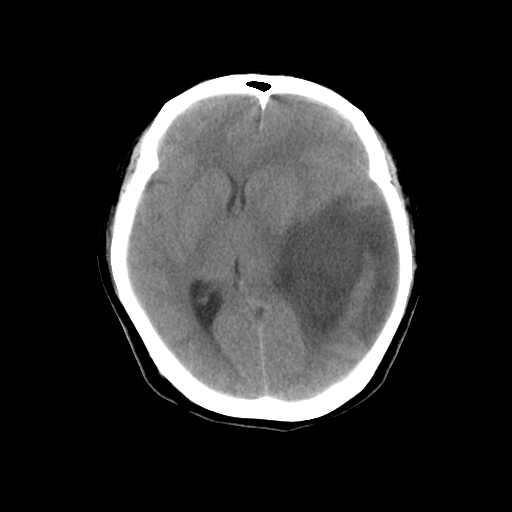

标题: CT14513:女性41岁,头部不适二月余,其它病史不详。请分析 [打印本页]

标题: CT14513:女性41岁,头部不适二月余,其它病史不详。请分析

1.考虑:左侧颞顶叶星形细胞瘤。2.大脑镰下疝。

左侧颞顶叶星形细胞瘤。

左侧颞顶叶星形细胞瘤,建议增强

1)考虑左侧颞顶叶胶质瘤。2)左侧颞顶部慢性硬膜下血肿?3)大脑镰下疝。